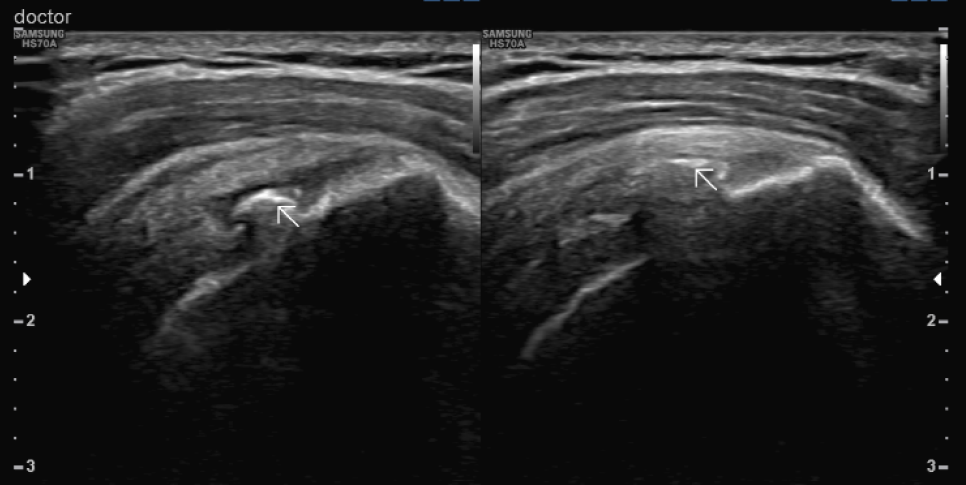

엑스레이와 초음파 검사상 환자의 양 어깨 회전근개(극상근, 견갑하근)에 석회 덩어리가 관찰되어 어깨의 움직임에 많은 제한이 있는 상태에서 관찰되었습니다. 이러한 것들을 석회성 근염이라고 하며, 유착성 피막염이라고 진단을 받게 되었습니다.

저는 통증이 오른쪽에만 있는 상태에서 충격파 치료는 오른쪽만 하도록 권유했습니다.그러나 환자는 이미 몇 번이나 충격파를 치고 있는데, 충격파 치료를 해야 하나 하고 싫어했습니다.

초음파검사가 검사하는 의사의 실력에 따라 검사 결과가 천차만별이듯이 충격파 치료도 어떤 브랜드와 등급의 기계를 사용하느냐에 따라 치료 효과가 달라진다고 설명하자 환자들은 수긍하고 치료를 시작했습니다.